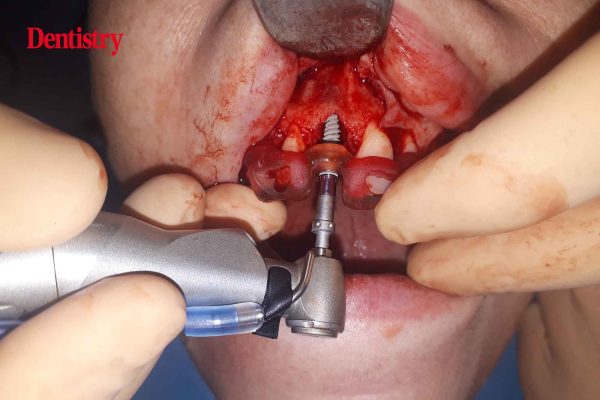

Guided implant surgery on a central incisor

Stephen Quinn shares the case of a patient requiring implant treatment following traumatic decoronation of the upper right central incisor.…

Set your implant skills free with guided surgery

Stephen Quinn delves into the benefits of guided implant surgery as an addition to the free-hand implant skillset. Awareness of…